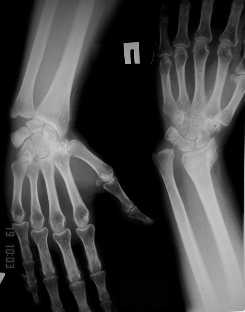

Уважаемые коллеги! Обратилась женщина, 55 лет. Травма 3 месяца назад, лечилась по месту жительства (Рис.1). Косорукость, боли, ограничение движений.

Досняли - рис.2-6. Хотелось-бы услышать мнения об объеме операции. С уважением, Юрий Алексеевич Булахтинглавный травматолог Камчатского Военно-морского госпиталя

u pazientki po nauchnomu ulna abutment/impingment syndrome posle posttraumaticheskogo ukorochenia radiusa

na rengene znachitelnoe ukorochenie radiusa, sustavnaia poverchnost naklonena dorsalno chresmerno , chetko vidno nekongruentnost DRUJ - distalnogo radioulnarnogo sustava ,ulna prosto vtikaetsia v triquetrum .